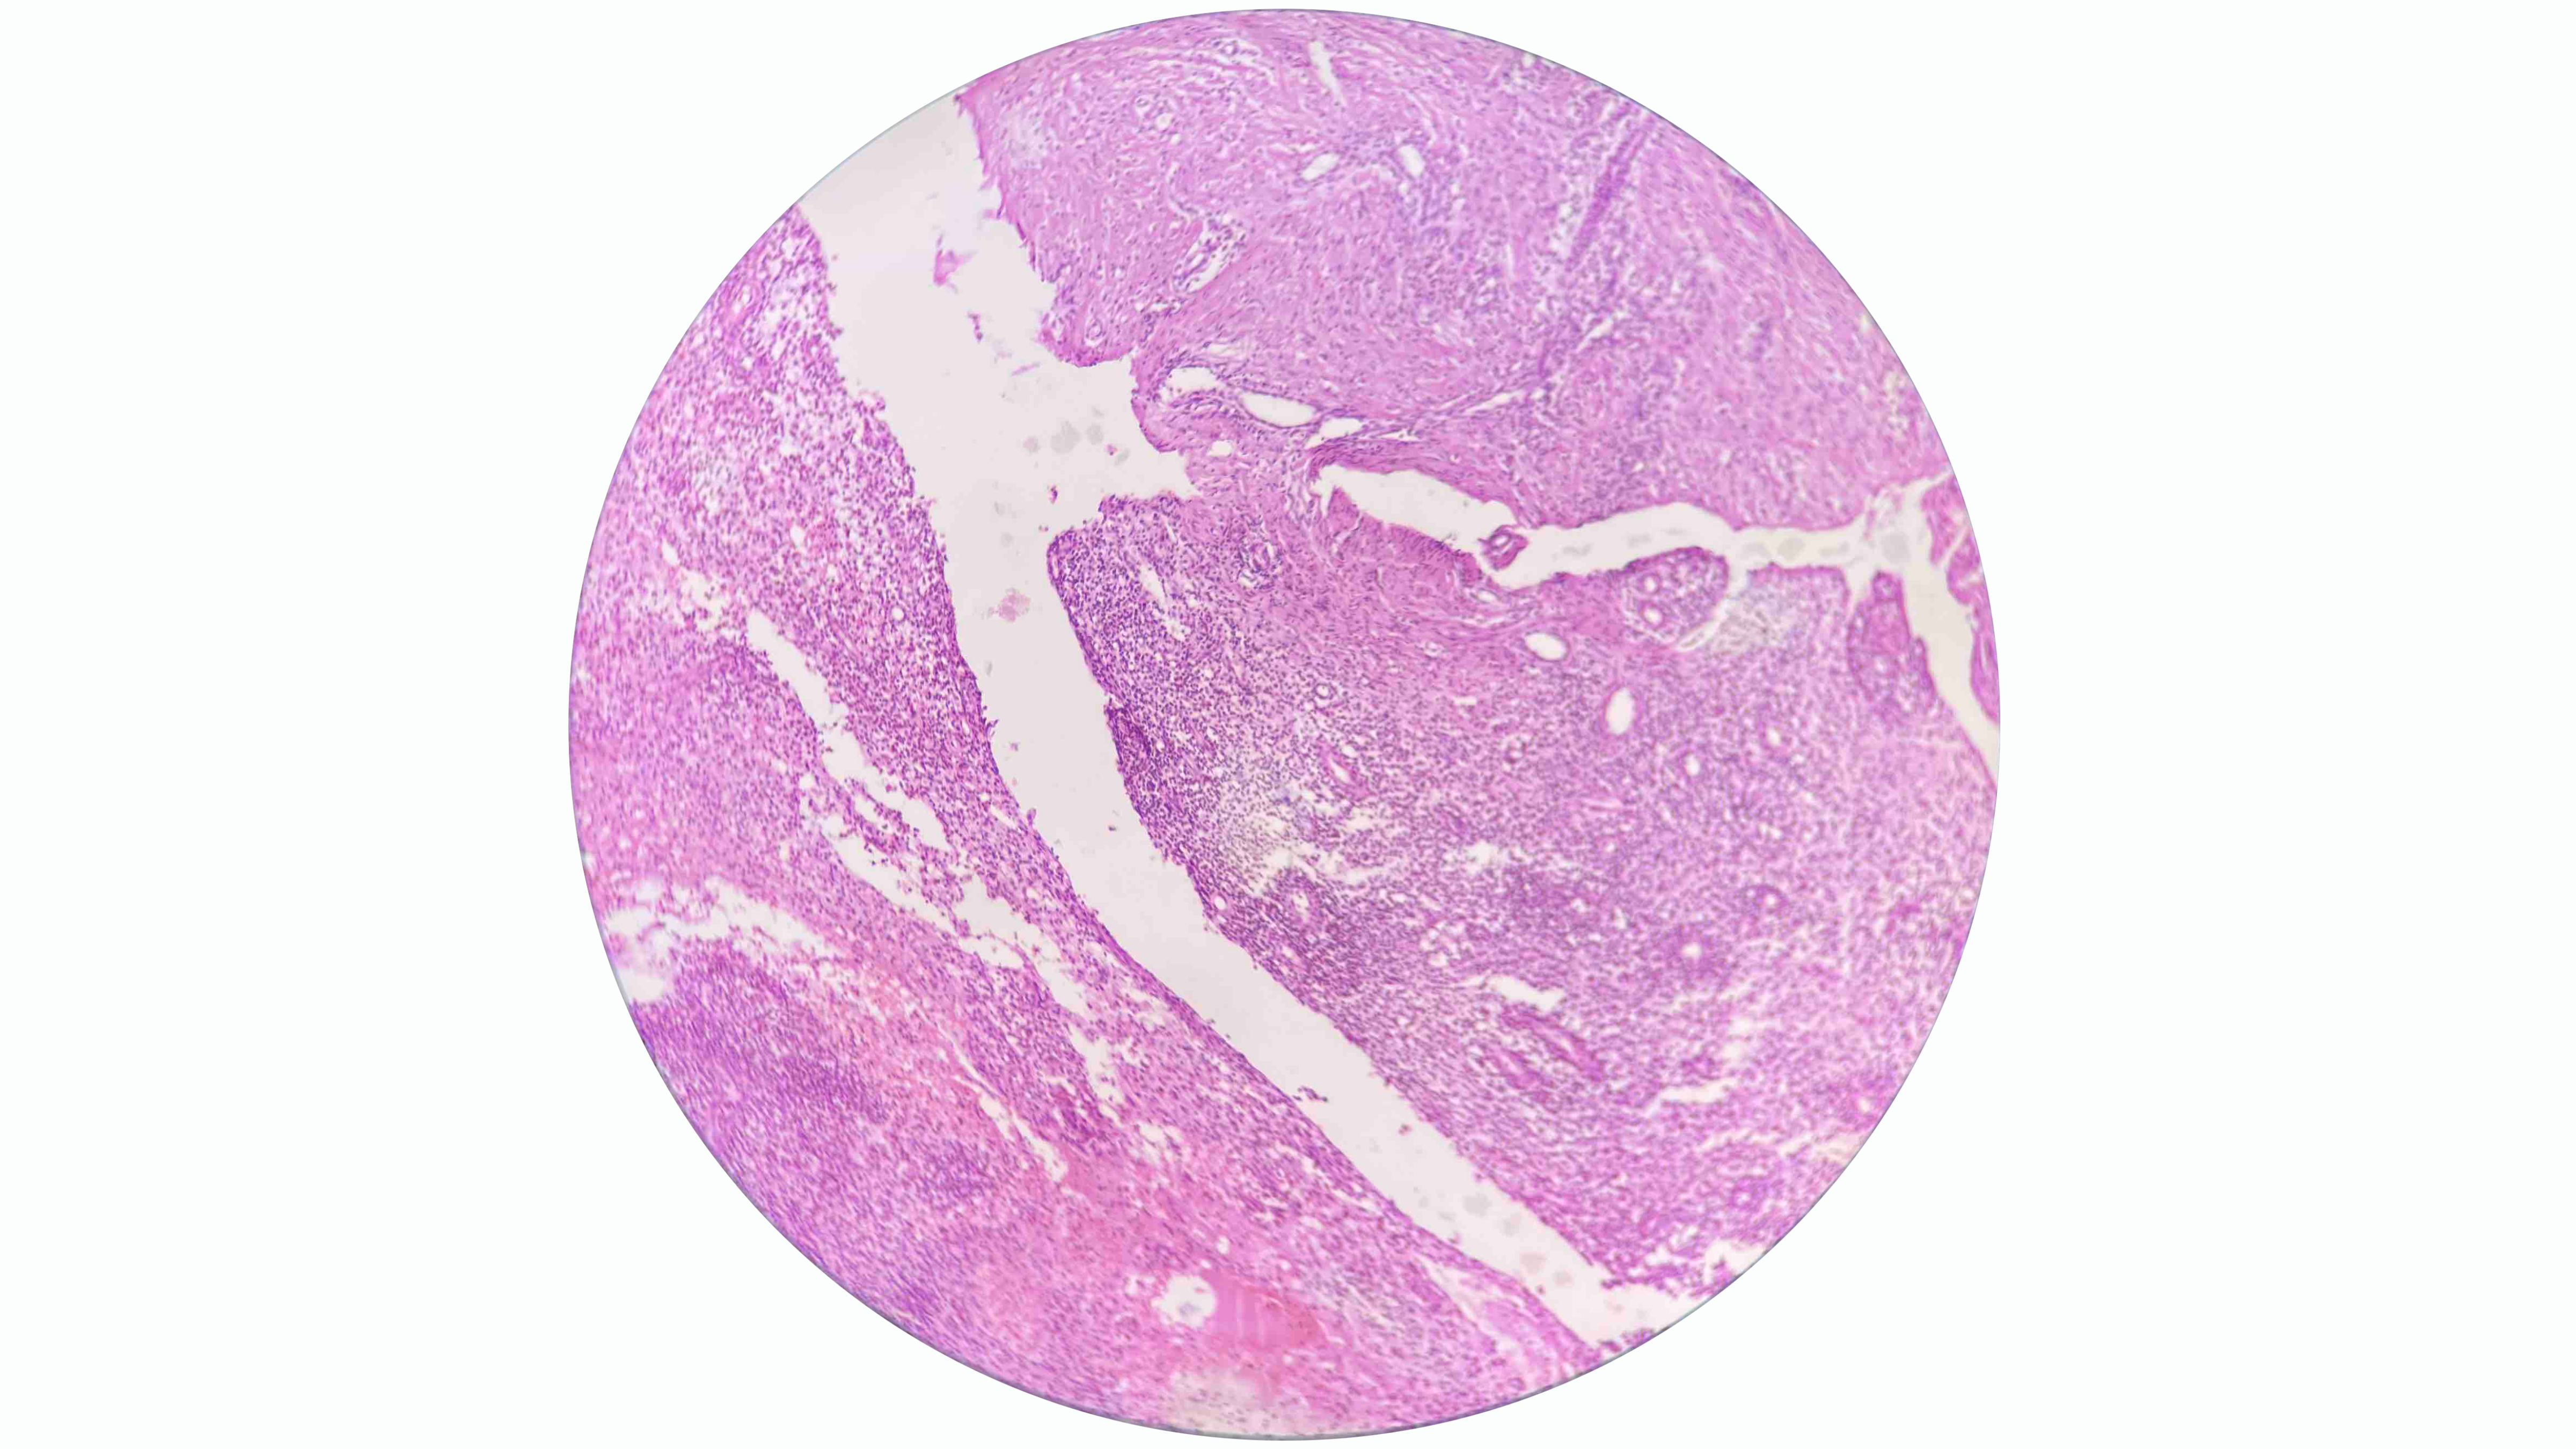

The primary diagnostic tool for thyroid nodules is FNA, which often leads to the misclassification of HTT as PTC or medullary thyroid carcinoma [9]. Ito et al. suggested that this diagnostic confusion arises from shared cytological features, including intranuclear cytoplasmic inclusions and nuclear grooves, which represent hallmark characteristics of PTC [4]. The cytological appearance of HTT on liquid-based preparations reveals cohesive aggregates or syncytial fragments of tumor cells surrounding hyaline material. Although tumor cells in HTT show enlarged nuclei with hyperchromasia and occasional intranuclear pseudo-inclusions similar to papillary carcinoma, HTT cells typically display dispersed fine chromatin rather than the pale and clear chromatin pattern observed in PTC [9].

Additionally, HTT cells demonstrate less frequent nuclear membrane irregularity and exhibit a more stratified trabecular arrangement compared to papillary carcinoma. These subtle distinctions prove crucial for accurate cytological interpretation, though they remain challenging to discern consistently in clinical practice [9]. Dell’Aquila et al. reported that up to 75% of HTTs are classified within Bethesda categories IV to VI [12]. Among the cases included, two were diagnosed as Bethesda category IV, while three were classified as category V, emphasizing their frequent misinterpretation by cytopathologists. Equivocal cytomorphologic diagnoses, such as atypia of undetermined significance or follicular lesion of undetermined significance, require repeat FNA, as the malignancy risk for nodules in these categories ranges from 1% to 15% [8].

On gross examination, HTT typically presents as a solid, well-circumscribed mass, or less commonly, as an encapsulated tumor, with colors ranging from yellow to tan, opposite to PTC, which is usually white and does not have a capsule. HTT generally lacks invasion into the capsule, vasculature, or thyroid parenchyma [5,7]. However, Gowrishankar reported a case in which invasion and malignant behavior were observed in HTT [13].

Immunohistochemistry can aid in diagnosing HTT, although some biomarkers used may lack significant specificity. HBME-1 and galectin-3 are well-established markers for malignant thyroid lesions, particularly PTC and its variants. However, their expression in HTT

remains a subject of debate. In their series, Dell’Aquila et al. found that the majority of HTT cases exhibited a distinct immune profile, with negative immunoreactivity observed in 16 out of 18 (89%) lesions. This finding further supports the classification of HTT as a benign tumor [12].

Recent genetic studies have demonstrated that GLIS rearrangements, particularly the PAX8-GLIS3 gene fusion, are critical for diagnosing HTT. Research indicates this fusion was present in 93% of HTT cases (13 out of 14), with the remaining 7% involving a PAX8-GLIS1 rearrangement. These findings highlight the diagnostic utility of detecting GLIS-related fusions to distinguish HTT from morphologically similar thyroid neoplasms [4].